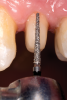

After determination of the desired post channel length (one-half to two-thirds the length of the canal), a dental dam was placed using the modified dam technique. The gutta-percha was removed with a series of preshaping instruments (Gates Glidden drills). The channel preparation for a prefabricated fiber-reinforced post (ie, the fiber-optic post system referred to earlier) was performed using a color-coded drill from this post system, establishing the desired intraradicular length and size for the selected post (Figure 11). The prepared channel was rinsed with water and dried with an endodontic paper point.

Fig 11. Channel preparation using color-coded drill.

Figure 11